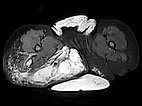

The corresponding axial, T2-weighted, fat-suppressed MRI of the pelvis at the level of the buttocks shows the massive extension especially of the lymphatic malformation in the right gluteal area. Additionally, persistent embryonic sciatic vein in the sense of a venous malformation is depicted.